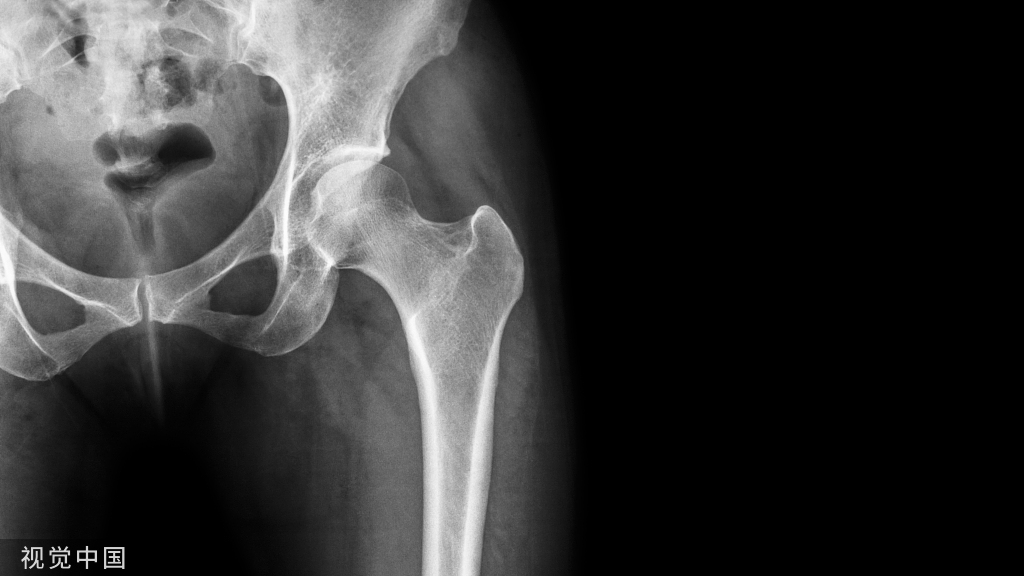

髌骨骨折分型

治疗方案的选择